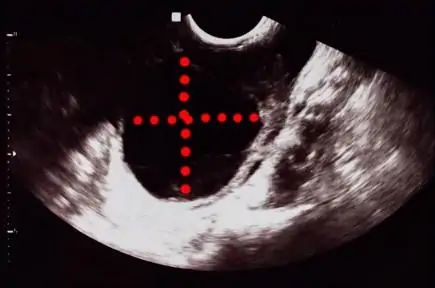

Na maioria das vezes esse cisto é identificado por exame de ultrassom, mas também é possível diagnosticar por tomografia, ressonância magnética e também por cirurgia.

Entendido os principais tipos de cisto benigno de ovário e as possíveis complicações, uma dúvida que angustia as mulheres após o diagnóstico de cisto de ovário é quando se deve suspeitar que o cisto de ovário pode ser um câncer de ovário. Existem dois aspectos importantes a serem avaliados.

O segundo aspecto são características dos tumores que podem ser vistas nos exames de imagem, como a presença de conteúdo sólido dentro do cisto, cisto irregular, muitos vasos sanguíneos, presença de septos, que são traves grossas no interior do cisto, dentre outras

Os exames de imagem conseguem ver também outros sinais sugestivos além do cisto, como presença de ascite que é a presença de grande quantidade de líquido na barriga, gânglios aumentados ou outras áreas suspeitas.